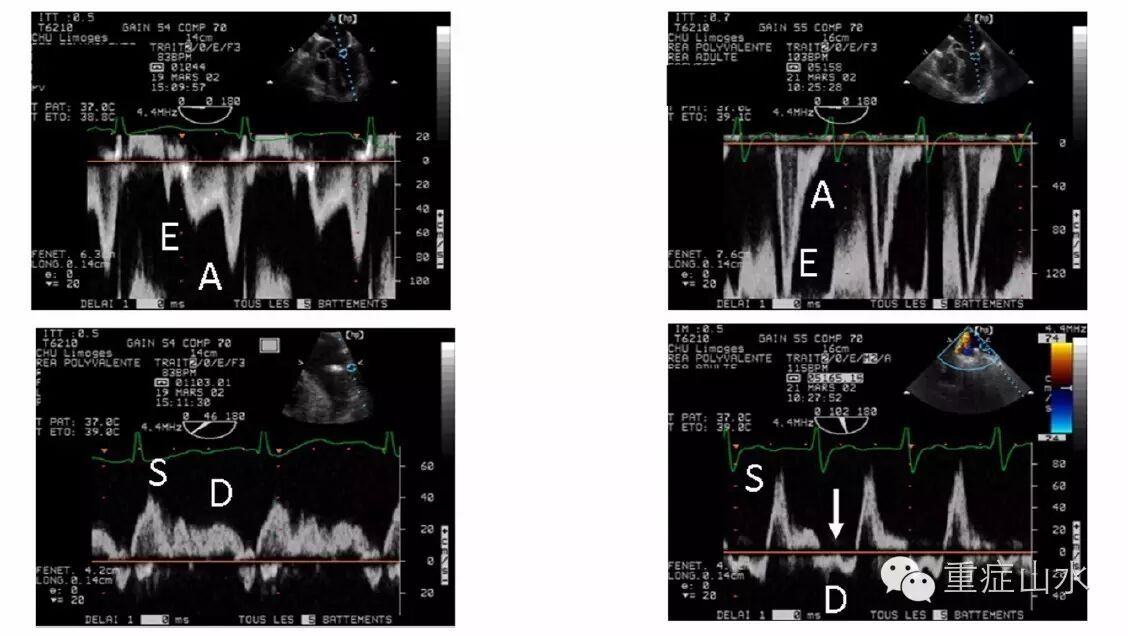

Fig. 2 Transesophageal echocardiographic hemodynamic monitoringin a patient with a known ischemic cardiomyopathy who failed ventilator weaning.Under pressure support, a trivial mitral regurgitation was disclosed by colorDoppler mapping in the two-chamber view (upper left), and leftcardiac filling pressures were low, as reflected by an inverted mitral E/ADoppler pattern (middle left) and a predominant pulmonary vein S wave (lower left). During thespontaneous breathing trial, a severe mitral regurgitation occurred (upper right), mitralDoppler pattern was restrictive (middle right), and pulmonary vein Doppler disclosed a reversed D waveconsistent with massive mitral insufficiency (lower right, arrow). The acute mitralregurgitation was attributed to a papillary muscle dysfunction secondary to atransient myocardial ischemic event. LA left atrium, La left auricle, LV left ventricle.Adapted from [7]

二尖瓣反流量在SBT时显著增加,可能导致脱机失败(Fig. 2)。